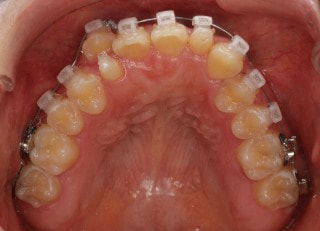

治療開始時

治療開始から25ヶ月後